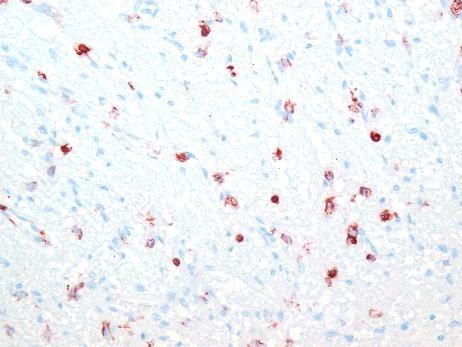

In cases of death caused by hypothermia, histological analysis can be used to determine the cause of death. Certain histological alterations of the pituitary glands in hypothermia have been reported in the literature, including haemorrhage, hyperaemia and cellular vacuolization of cells in the anterior lobe. In the present study, the validity of these morphological alterations as markers for fatal accidental hypothermia was investigated in autopsy material. A total of 34 pituitary glands in cases of verified fatal accidental hypothermia were examined histologically (haematoxylin and eosin, ferric, azan) and immunohistochemically (LCA, ACTH, C5b-9). The findings were compared with 61 cases in a control group. Hyperaemia was found in 50.0% of the study group cases and 59.0% of the control group cases. Cellular vacuolization was observed in one case (2.9%) in the study group and one case (1.6%) in the control group. Acute or recent haemorrhage in the glandular tissue was never detected. In our study, the histopathological characteristics described in the literature as pathognomonic for hypothermia could not be confirmed. Furthermore, histological differences in the pituitary glands between fatal hypothermia cases and control group cases were not observed.

在低温致死的案例中,组织学分析可用于确定死因。文献中已报道了低温状态下垂体的某些组织学改变,包括前叶出血、充血以及细胞空泡化。在本研究中,利用尸检材料对这些形态学改变作为意外低温致死标志物的有效性进行了调查。对34例经证实的意外低温致死案例的垂体进行了组织学检查(苏木精和伊红染色、铁染色、偶氮染色)和免疫组织化学检查(LCA、促肾上腺皮质激素、C5b - 9)。将结果与对照组的61例案例进行了比较。研究组50.0%的案例和对照组59.0%的案例发现有充血。研究组有1例(2.9%)观察到细胞空泡化,对照组有1例(1.6%)观察到细胞空泡化。从未在腺组织中检测到急性或近期出血。在我们的研究中,文献中描述为低温特征性的组织病理学特征无法得到证实。此外,未观察到低温致死案例与对照组案例在垂体方面的组织学差异。